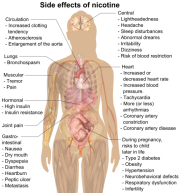

| 21:31, 23 במרץ 2024 | ניקוטין1.png (קובץ) |  |

276 קילו־בייטים | Motyk | 1 | |

| 03:32, 23 במרץ 2024 | Nicotine.jpg (קובץ) |  |

905 קילו־בייטים | Motyk | 1 | |